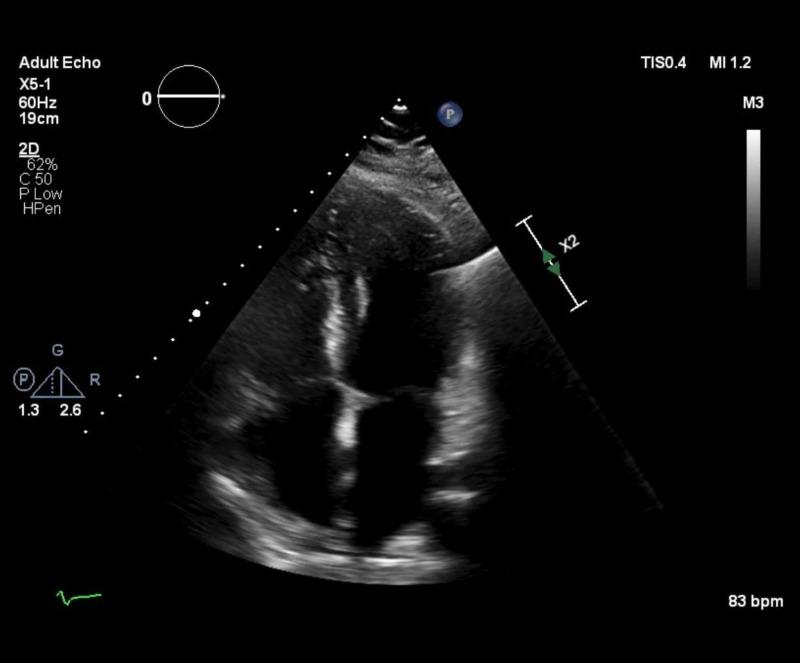

As the COVID-19 pandemic evolves, the medical community continues to discover novel clinical manifestations of the severe acute respiratory syndrome coronavirus 2 (SARS-CoV-2) virus. Often, extrapulmonary manifestations occur simultaneously with pulmonary disease. However, there is a paucity of literature describing the cardiac manifestations of COVID-19 in the absence of pulmonary findings. We report a rare case of acute pericarditis presenting with pericardial effusion and cardiac tamponade in a 43-year-old man diagnosed with COVID-19. This case emphasizes the importance of continued investigation regarding diagnosis and treatment of COVID-19 and its related symptoms.

随着新冠疫情的演变,医学界不断发现严重急性呼吸综合征冠状病毒2(SARS-CoV-2)的新临床表现。通常,肺外表现与肺部疾病同时出现。然而,在没有肺部表现的情况下,描述新冠病毒心脏表现的文献很少。我们报告了一例罕见病例,一名43岁确诊为新冠病毒感染的男性出现急性心包炎并伴有心包积液和心脏压塞。该病例强调了持续研究新冠病毒及其相关症状的诊断和治疗的重要性。